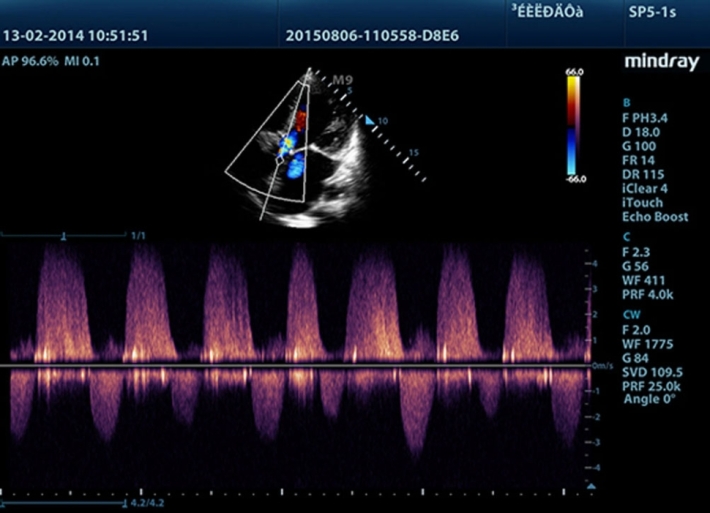

Медицинское оборудование и сервисное обслуживание